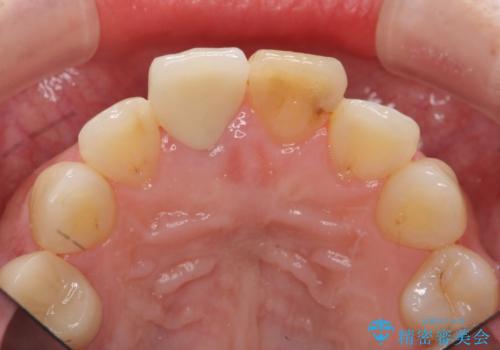

リアルな歯の色調にこだわるオールセラミッククラウン治療

天然歯を再現したリアルな仕上がりに満足いただくことができました。

オールセラミッククラウン スペシャルプランは細やかな色調の再現に優れ、目立つ前歯の審美的な仕上がりがより達成されやすいプランです。